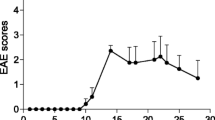

18F-FOL and 11C-PBR28 radioligands are able to detect fDTH-EAE lesions, but only 18F-FOL can differentiate between acute and chronic lesions

Both 18F-FOL and 11C-PBR28 radiotracers were able to detect the inflammatory fDTH-EAE lesions (Figs. 2, 3, and 4). In vivo PET/CT imaging with 18F-FOL and 11C-PBR28 showed focal uptake in the induced brain hemisphere, which was co-localized with the MRI-depicted lesion. Tracer kinetics, i.e., time-activity curves (TACs), revealed a significant difference between the lesion and contralateral hemispheres in all studied groups (P < 0.0001, Fig. 4a). In the chronic phase, 18F-FOL showed significantly higher uptake than 11C-PBR28 (P = 0.016, Fig. 4a, b) at the lesion site, but no other differences between the tracers or the acute and chronic phases were observed. A significant correlation was observed between in vivo and ex vivo measurements of both 18F-FOL and 11C-PBR28 tracers (18F-FOL: R = 0.95, P = 0.0004, 11C-PBR28: R = 0.76, P = 0.037, Fig. 4c).

In vivo multimodal imaging of fDTH-EAE rat brain at acute (day 14) and chronic (day 90) phases of disease development with quantitative data. a Representative coronal MRI, 18F-FOL, and 11C-PBR28 PET/CT images and corresponding time-activity curves. White arrows denote inflammatory lesions. All PET images are displayed using the same color scale. Tracer uptake in the lesion is significantly higher than that in the contralateral site. ***P < 0.001. b Quantitative PET data presented as SUV ratios reveal significant differences between tracers in the chronic phase, but not in the acute phase. *P < 0.05. c Comparison of in vivo and ex vivo PET data. SUV ratio = SUVmax(lesion)/SUVmean(contralateral). R2 is Spearman’s correlation coefficient. Error bars denote standard deviation